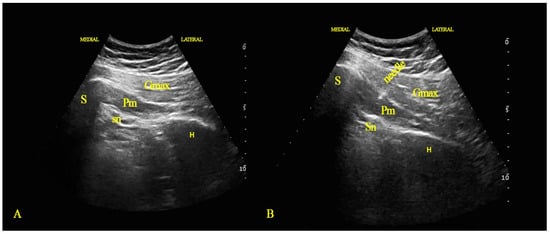

2.1. Injection Technique